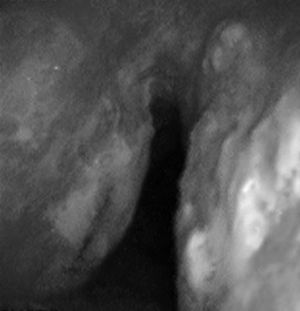

Caso 2Mujer de 57 años con episodios repetidos de expectoración hemoptoica sin otra sintomatología acompañante. Tenía antecedentes de hipertensión arterial en tratamiento con valsartán, obstrucción nasal crónica y sin hábitos tóxicos. La exploración física fue normal, así como las pruebas complementarias realizadas: analítica y radiografía torácica. Se realizó broncoscopia, detectándose múltiples nódulos en las caras anterior y posterior de la tráquea friables y sangrantes, uno de ellos ulcerado (fig. 2). El estudio anatomopatológico demostró la presencia de material amorfo eosinófilo que presentaba birrefringencia con luz polarizada correspondiente a material amiloide. Se realizó estudio de extensión de la enfermedad, detectándose también material amiloide en la grasa subcutánea y en la biopsia de médula ósea, quedando diagnosticada de una amiloidosis primaria sistémica con afectación pulmonar y de médula ósea.

El paciente del caso 1 fue tratado en 2 ocasiones con láser Nd:YAG para la repermeabilización de la vía aérea (fig. 1B), debido a la estenosis que presentaba por infiltración amiloide, con lo que se consiguió una mejoría clínica y funcional del paciente. En cuanto a la paciente del caso 2, recibió tratamiento con una combinación de prednisona y melfalán, con buena respuesta y resolución parcial de las lesiones traqueales sin afectación funcional ni sintomática.